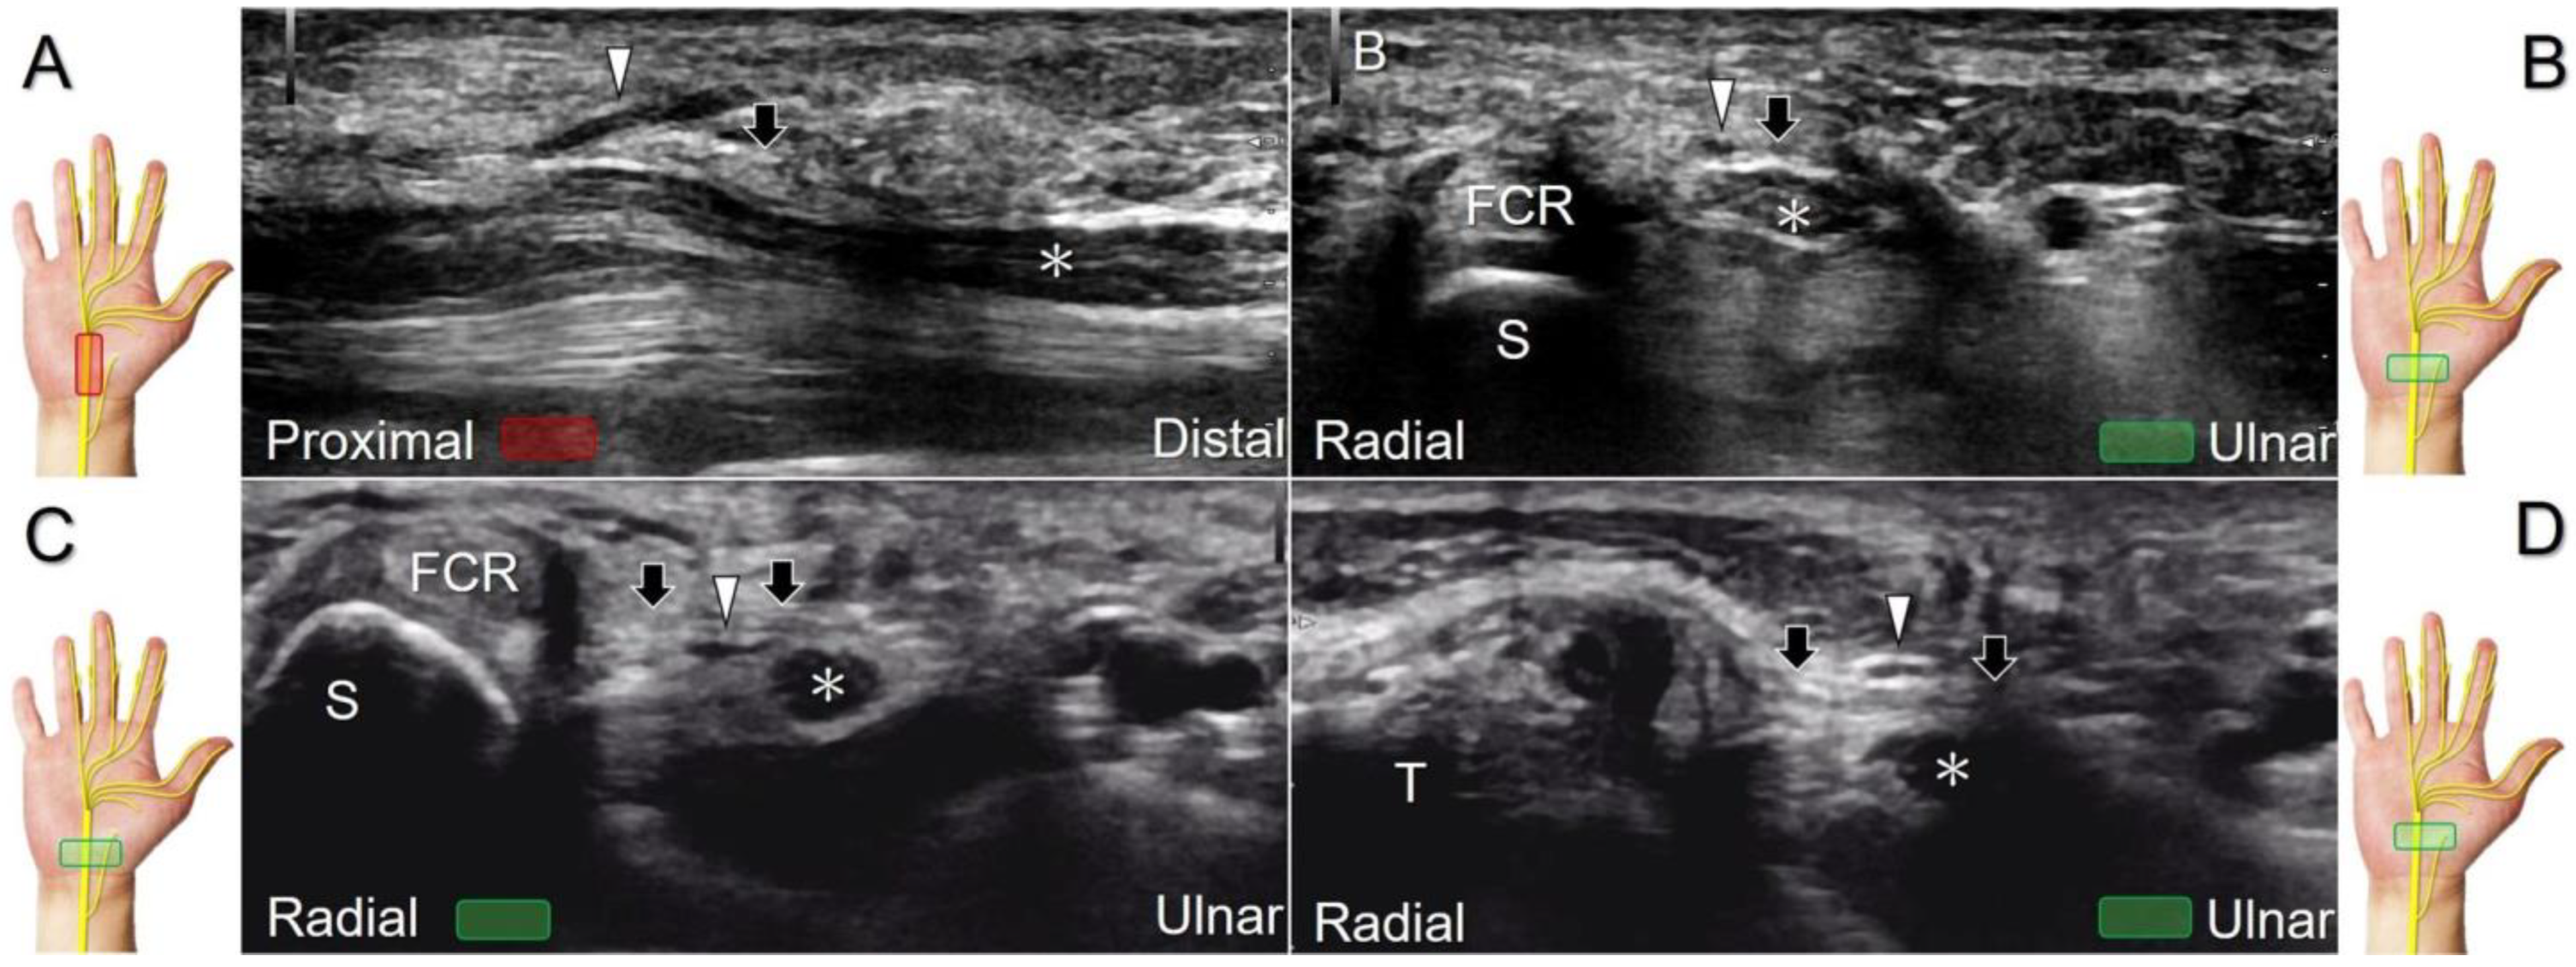

The transducer can be placed in the axial plane on the distal one-third of the forearm with the forearm supinated. The median nerve travels between the flexor digitorum superficialis and flexor digitorum profundus muscles. It gradually runs superficially to enter the carpal tunnel. The carpal tunnel inlet is defined as the plane crossing the scaphoid and pisiform (Figure 2A), whereas the plane linking the trapezium and hook of the hamate serves as the carpal tunnel outlet (Figure 2B).

Clinical Implication

Carpal tunnel syndrome is the most common entrapment neuropathy whereby the median nerve is entrapped by various causes, like hypertrophy of the flexor retinaculum (Figure 2C,D) and compression from the accessory muscles, swollen tendons, ganglions, and bony fractures within the tunnel. Ultrasonographic changes encompass swelling proximal to the entrapment site (Figure 3A), flattening over the entrapment site (Figure 3B), intraneural hypervascularity (Figure 3C), and focal loss of the trimline pattern (Figure 3D).

Figure 2. Sonographic/normal imaging of the median nerve from the inlet (A) to the outlet (B) of the carpal tunnel. Hypertrophy of the flexor retinaculum at both the inlet (C) and outlet (D) of the carpal tunnel. Asterisk: median nerve; small white arrowheads: normal flexor retinaculum; large arrowheads: hypertrophy of the flexor retinaculum. FCR: flexor carpi radialis; S: scaphoid; P: pisiform; T: trapezium; H: hook of the hamate.